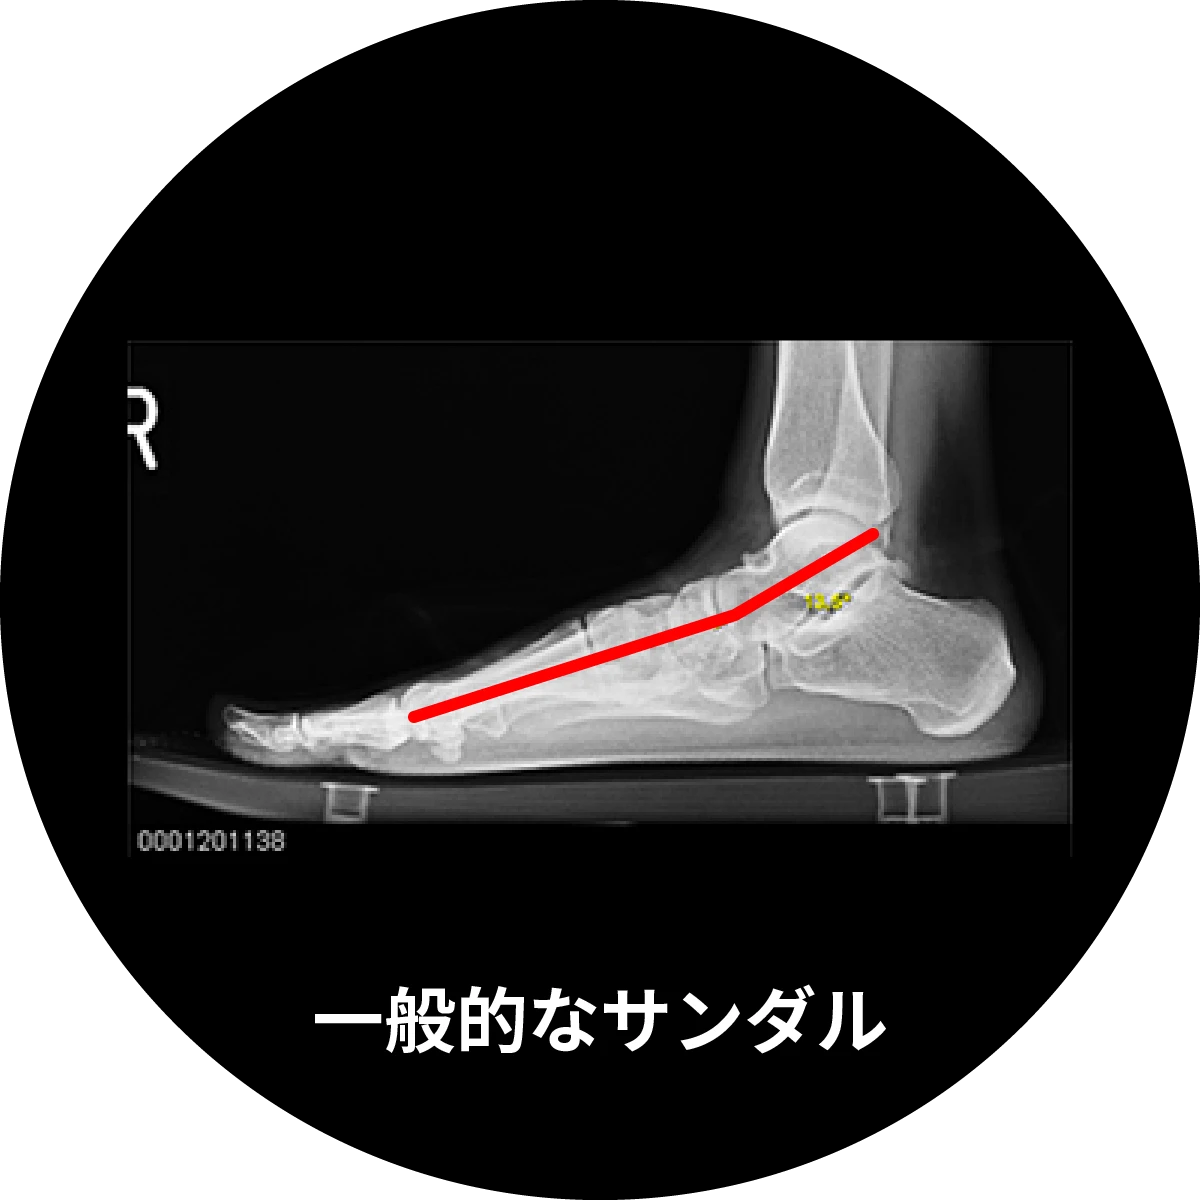

レントゲンによる荷重位撮影

赤い線のメアリーズアングルの角度が増大していることから、しっかりアーチがサポートされていることがわかる。

アーチをサポートすることは、踵周りの関節が過剰に動きすぎる過剰回内を抑制する効果があります。過剰回内(オーバープロネーション)が起こると、アーチ構造を崩すと同時に、スネの正しい角度や向きをいびつに変化させ、膝や腰をはじめ体全体にも悪影響を及ぼします。

スポーツにおけるパフォーマンスの低下だけでなく、怪我や疲れも誘発してしまうのです。

- 荷重位撮影:立っている時の足の裏にかかる圧力の動きを計測して撮影

- メアリーズアングル:足のアーチサポートを評価する角度